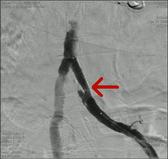

可怕的LEADDP 糖尿病下肢血管病变(LEADDP)可致患者肢体麻木、疼痛,间歇性跛行,乃至坏疽(糖尿病足),截肢率高达40 %以上。LEADDP是糖尿病致残、致死的主要原因,糖尿病患者因LEADDP造成的截肢,要比非糖尿病患者高5到10倍以上。先进的DSA + 微创介入 1、选择性血管造影(DSA)是LEADDP诊断的金标准。 2、微创介入治疗优点: 创伤小,仅有一2-3 mm的穿刺创口 成功率高:目前其成功率达85-90 % 保肢率高:术后病人截肢率可从40 %降为4 %左右 早发现早治疗:越早治疗效果越好.独创的微创介入 + HBO + bFGF综合治疗途径 1、DSA + 微创介入 2、高压氧(HBO)物理疗法:大型空气加压舱,治疗压力0.2 MPa,面罩吸纯氧30 min 3、基于重组成纤维细胞生长因子(bFGF)局部换药. |